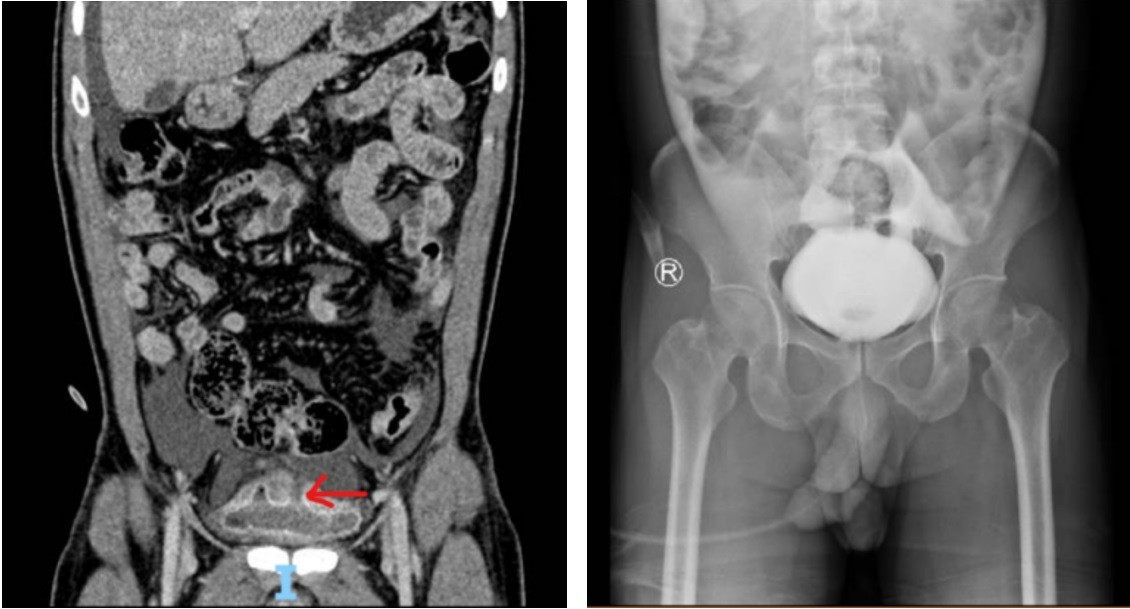

Theo bệnh sử, trong lúc uống rượu bia, bệnh nhân nhịn tiểu lâu, khi vào nhà vệ sinh thì bị trượt ngã và vùng hạ vị va đập mạnh vào thành bồn cầu. Khoảng 4 giờ sau tai nạn, gia đình mới đưa bệnh nhân đến Bệnh viện Nhân Dân 115. Chẩn đoán hình ảnh cho thấy có dịch tự do trong phúc mạc và vỡ bàng quang ở vòm bàng quang, kèm chấn thương gan độ I.

Hình ảnh bàng quang bệnh nhân bị vỡ (bên trái) và sau phẫu thuật (ảnh bên phải)

Vỡ bàng quang trong phúc mạc chiếm khoảng 30% và thường xảy ra khi bàng quang căng đầy, bắt buộc phải phẫu thuật khâu phục hồi. Vỡ ngoài phúc mạc chiếm đa số (khoảng 60%), thường kèm gãy xương chậu và có thể được điều trị bảo tồn trong một số trường hợp. Vỡ phối hợp chiếm khoảng 10% và là những trường hợp phức tạp buộc phải can thiệp ngoại khoa. Trường hợp tại Bệnh viện Nhân Dân 115 thuộc loại vỡ trong phúc mạc, được can thiệp kịp thời nên hồi phục tốt.